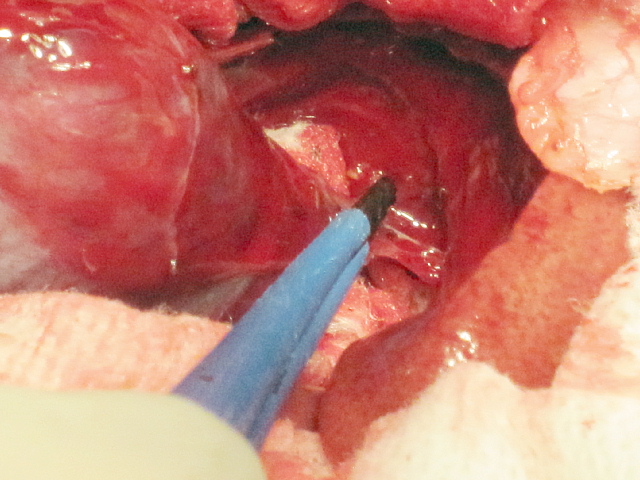

いつも通り胆嚢を牽引しつつ肝臓から剥離していきます。

先週の症例に比べるとずっと軽症ですから剥離は順調に行ったのですが・・・

胆嚢頚部のところでの結合組織増生が顕著であり、これが硬いものですから超音波乳化吸引装置では歯が立ちません。

その場合、電気メスバイポーラを使用して結合組織を切断します。